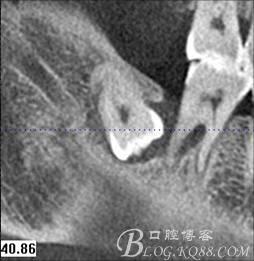

圖1. 47牙冠的近中面緊鄰下頜神經(jīng)管

圖3.通過(guò)矢狀面和冠狀面來(lái)判斷48與下頜管及47的關(guān)系